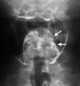

Postcricoid carcinoma